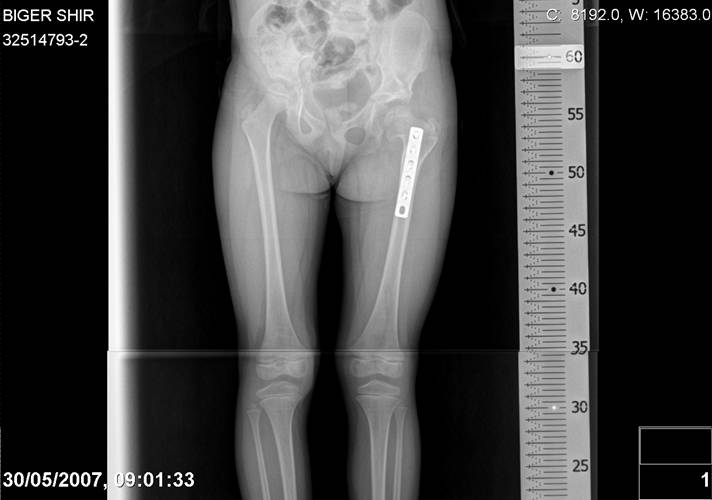

Chto by ne byt goloslovnym posilau vam svoi sluchai gde sdelal vse chto napisal vyshe